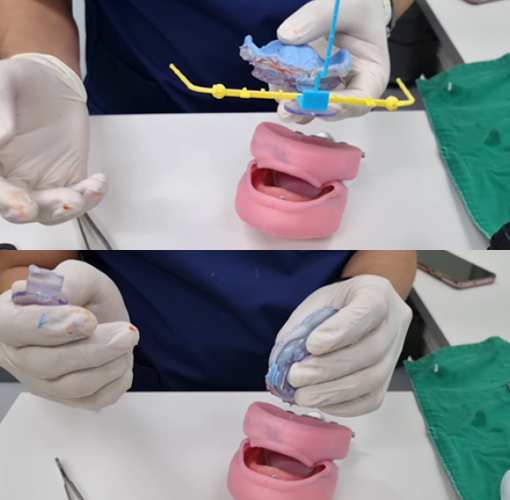

Apply JB Fork to maxilla with putty and VPS

Check for upper lip support and attach anterior teeth

Apply JB Fork to mandible with putty and VPS

Apply JB Fork to maxilla with putty and VPS

Check for upper lip support and attach anterior teeth

Apply JB Fork to mandible with putty and VPS

Apply JB Fork to upper and lower jaws

Gothic arch tracing

Bite taking

Apply ADD POP BOW

Apply JB Fork to upper and lower jaws

Gothic arch tracing

Bite taking

Apply ADD POP BOW